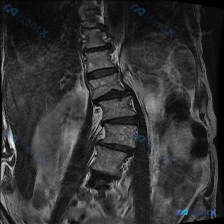

整理到一张腰椎MRI-T1序列冠状位的影像资料,先不说是啥结论,大家看看第一眼会怎么考虑? 现有影像能看到的点: 1. 腰椎明显向右侧弯畸形 2. 多节段椎间隙变窄,下腰段(L4-L5、L5-S1)更明显,边缘有骨赘 3. 各腰椎椎体信号不均匀,里面有散在的、片状/斑点状的T1低信号影(对比周围的高...

网上看到一张腰椎MRI-T1序列冠状位的影像资料,先不直接说影像科给的结论,大家第一眼读一下: 主要能看到什么表现?第一反应会先往哪个方向考虑?有没有容易忽略的细节或者需要警惕的点?